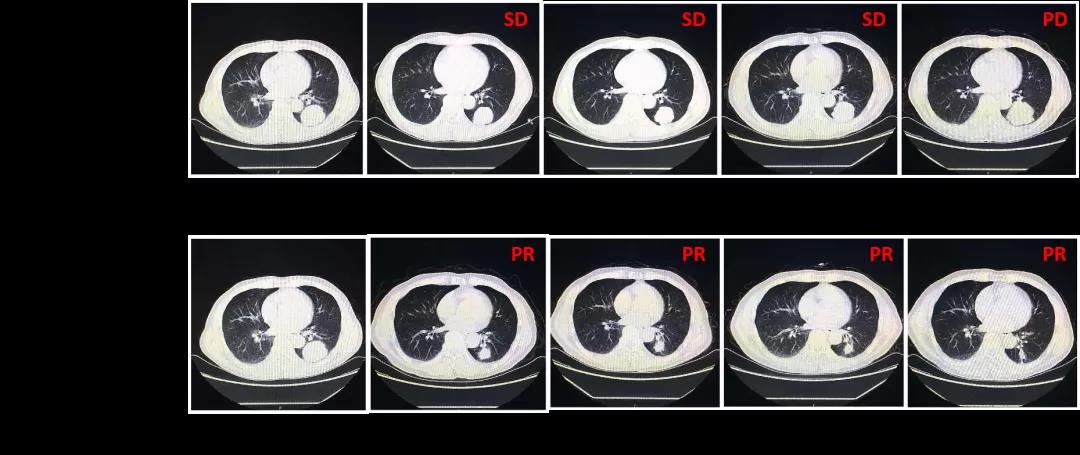

患者入组至对照组后,化疗7个疗程,疗效评估均为SD。第8个疗程,疗效评估PD。后交叉入组至卡瑞利珠单抗治疗组,第1个周期疗效即达PR,此后持续治疗8个周期,疗效均为PR。